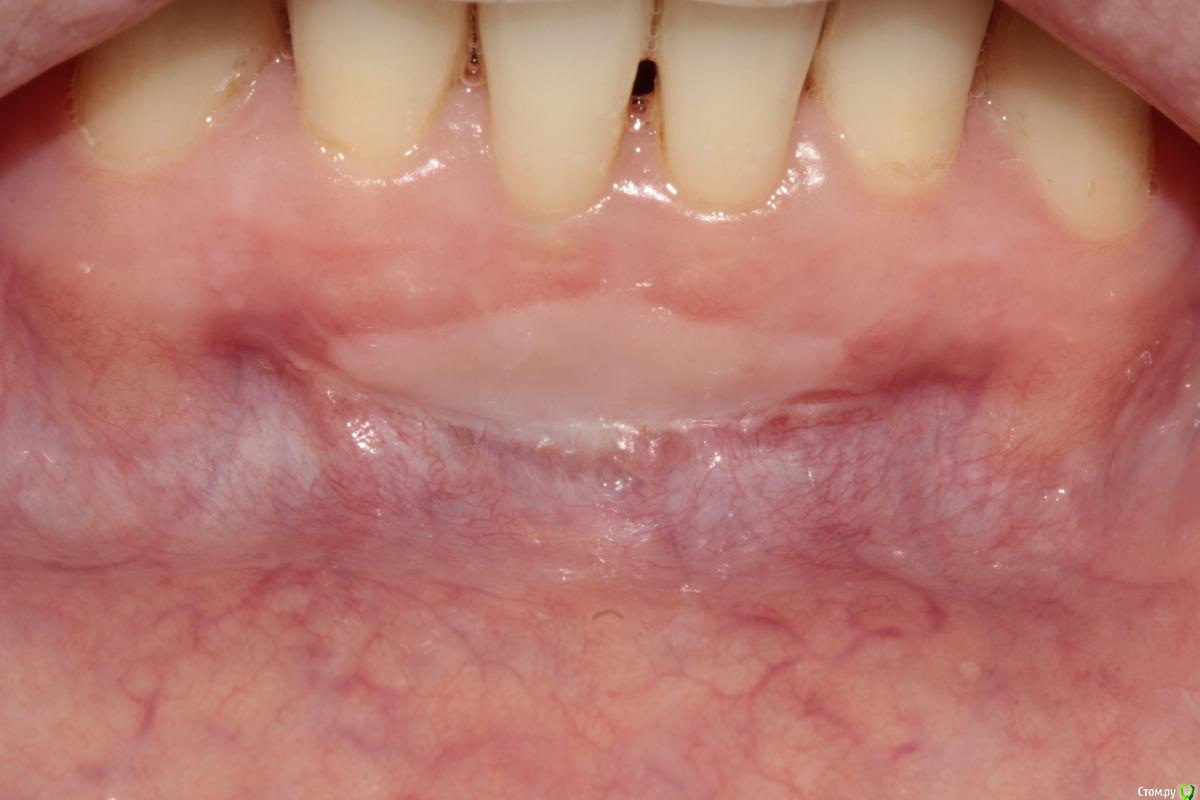

Rafael_Gogyan Опубликовано 16 февраля, 2015 Поделиться Опубликовано 16 февраля, 2015 ИМХО, не было показаний для данной операции Господа, кто как чаще делает вестибулопластику на нижней челюсти. Эдлан- Мейхер или СДТ? понятие "вестибулопластика" существует наверное только в России. Делать его просто так для профилактики не нужно. По Эдлану-Мейхеру мы не получаем прикрепленную кератинизированную десну. А просто углубить преддверие это ничего не значит. При отсутствии ЗПКД как вариант можно СДТ. Но, опять же, применяя увеличение и микрохирургию при рецессиях в области нижних резцов чаще используют туннельные методики. Без рубцов. И заживление более комфортное для пациента. Ссылка на комментарий

Чертков Александр Опубликовано 11 февраля, 2015 Поделиться Опубликовано 11 февраля, 2015 (изменено) увеличение ЗПКД, профилактика рецессии, при улыбке не видноЕсть более "эстетичные" и менее инвазивные способы. Рецессии?...Где? Я бы такой уровень уздечки даже и не подумал как-то изменять. А если уж очень хочется, то можно было выполнить довольно простую френотомию(эктомию). Минусы я полагаю Вы и сами видите. [/quote Вы имеете ввиду отличие по цвету?Нет, цвет - дело второстепенное, а вот два грубых рубца получили...тем самым, действительно, поспособствовали возможности рецессии. Изменено 11 февраля, 2015 пользователем Чертков Александр Ссылка на комментарий

Dc.Petrov Опубликовано 12 февраля, 2015 Автор Поделиться Опубликовано 12 февраля, 2015 Никаких показаний к хирургии нет Не согласен, мб на фото не видно, но СДС у 31,41 не более 1-2 мм от края маргинальной десны.При инфильтрации анестетика это особенно очевидно. Условия для рецессий есть. Надо было просто биотип утолщить Согласен вот два грубых рубца получили...тем самым, действительно, поспособствовали возможности рецессии ? Не совсем понял Ваше утверждение. Буду наблюдать в отдаленные сроки. Если Вам интересно продолжу тему с фото через 3, 6, 12 месВсех благодарю за комментарии Ссылка на комментарий